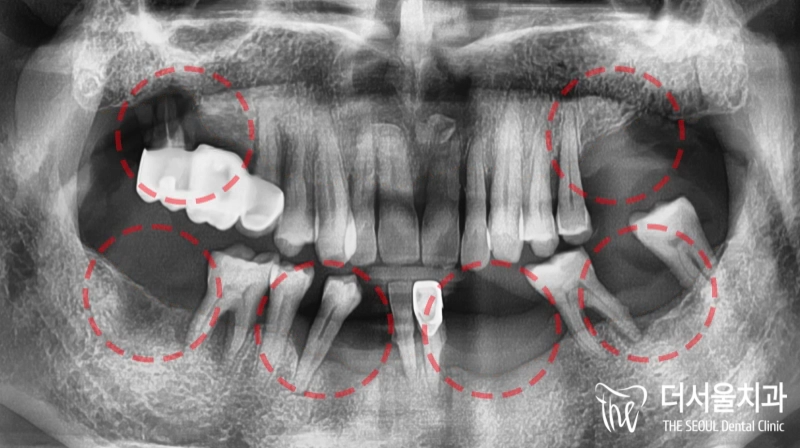

반갑습니다. 태평동 더서울 치과 입니다. 많은 분께서 이런 생각을 가지고 있으실 겁니다. ‘잇몸뼈 문제로 치아가 떨어졌다면, 임플란트 심는게